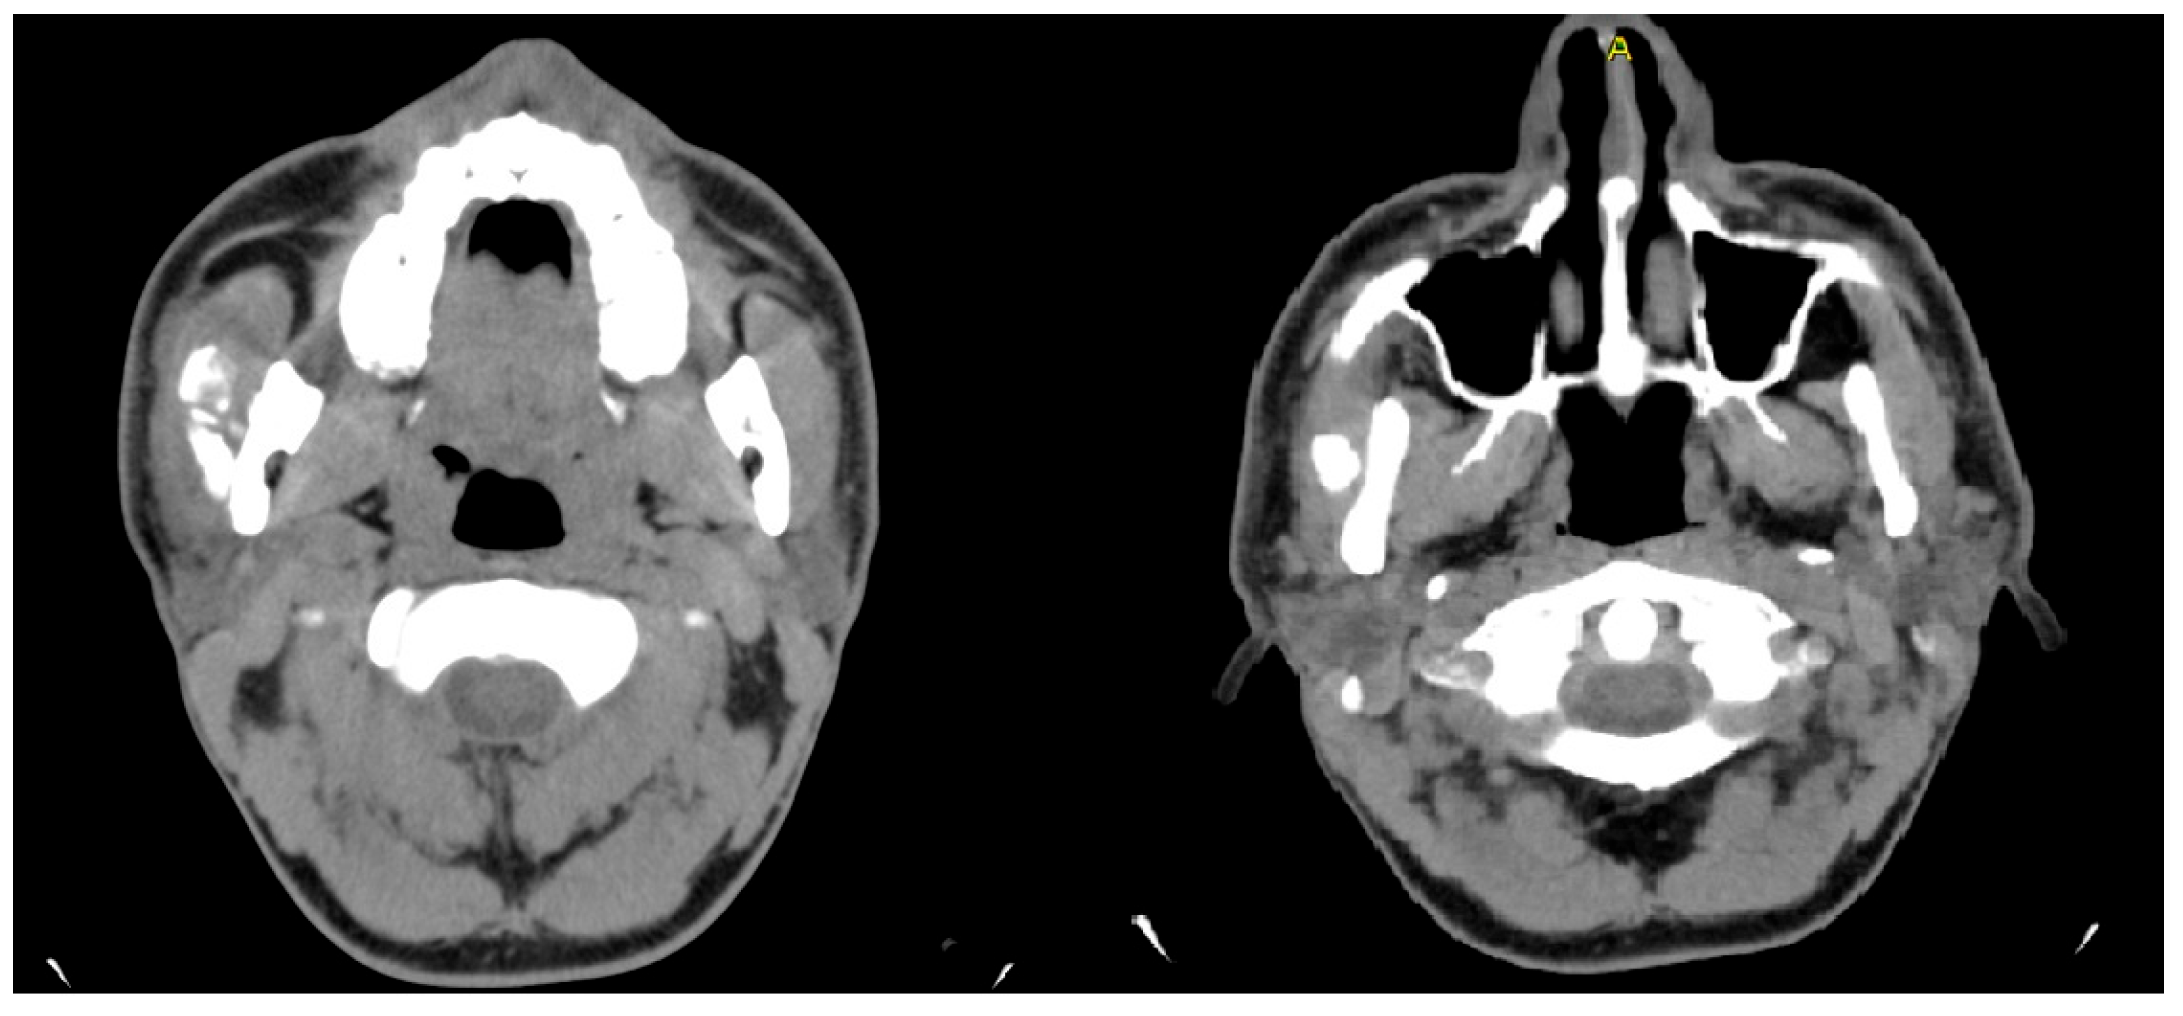

- Case 1

- Case 2

- Case 3

- Case 4

- Case 5